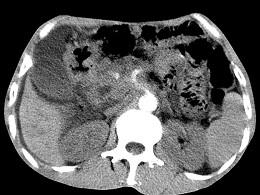

问题 女,50岁,中上腹疼痛,消瘦乏力,影像检查如下图,最佳的诊断是 ( )

选项 A、胰岛素瘤 B、腹膜后淋巴瘤 C、急性胰腺炎 D、胰腺癌并腹膜后淋巴结转移 E、慢性胰腺炎

答案 D